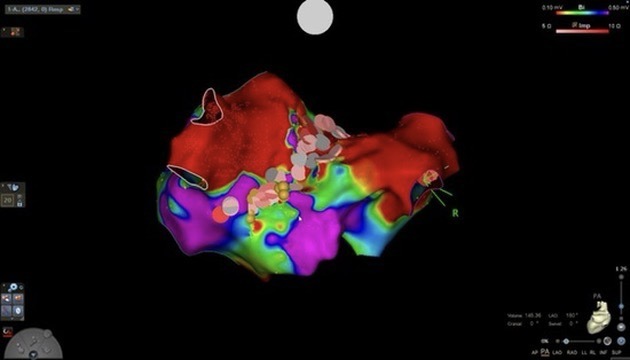

Imagen de un mapa electroanatómico tridimensional del corazón, utilizado durante un procedimiento de ablación por fibrilación auricular. Este sistema permite al electrofisiólogo identificar con precisión las zonas responsables de la arritmia, visualizar la actividad eléctrica en tiempo real y aplicar tratamiento dirigido para restaurar el ritmo cardíaco normal de forma segura y efectiva.

En Cardiac & Vascular, el abordaje del Dr. Nicolás Reyes se basa en:

- Seguimiento clínico cercano

- Evaluación individualizada

- Tecnología de mapeo electroanatómico

- Protocolos de seguridad avanzados